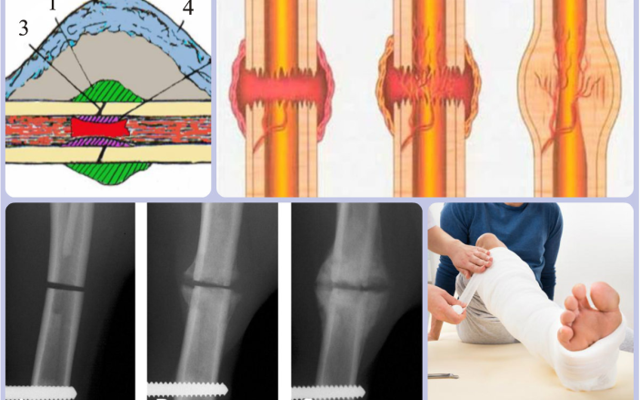

Этапы образования костных мозолей

Этапы формирования нароста

Костная мозоль не болит, а внутри нет признаков воспалительного процесса. Формирование аппендикса — один из этапов реконструкции кости. Можно выделить следующие этапы:

- На кости появляются периостальные и внутрикостные мозоли. Для них не характерны воспалительные процессы.

- Мозоли надкостницы рассасываются спонтанно.

- Образование промежуточных мозолей.

- При правильном лечении натоптыши спонтанно рассасываются и исчезают.

- Регенерация поврежденной кости.

После травмы в поврежденном месте происходит автолиз. Мягкие ткани по разным причинам имеют свойство отмирать. В результате происходит активация и миграция лейкоцитов, развивается сильный отек. Эти симптомы возникают сразу после травмы и перелома.

Сильная болезненность появляется на четвертые сутки. Затем клинические симптомы постепенно утихают, образуется хрящ, который позже замещается костной мозолью. Эти пучки становятся причиной образования компактного вещества. Кровеносная система полностью восстановлена.